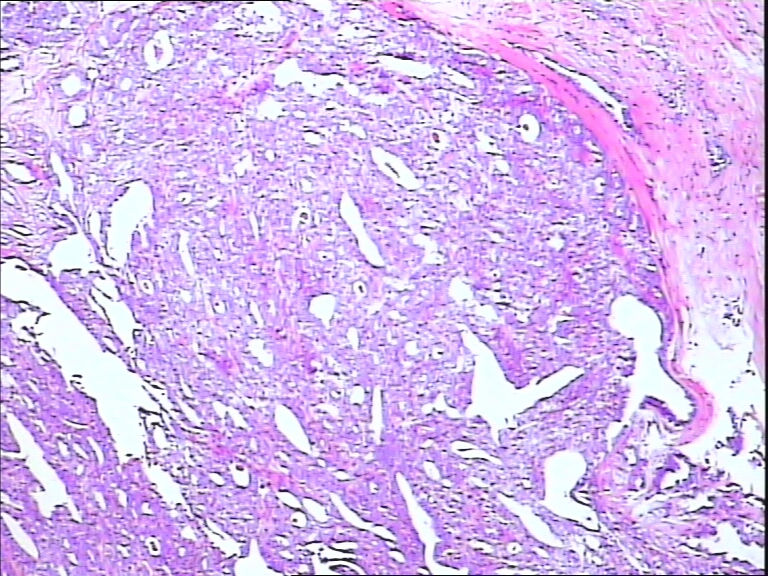

42y

左乳头有3mm结节

灰白不整形组织一块:0.7*0.5*0.4

导管内乳头状肿瘤